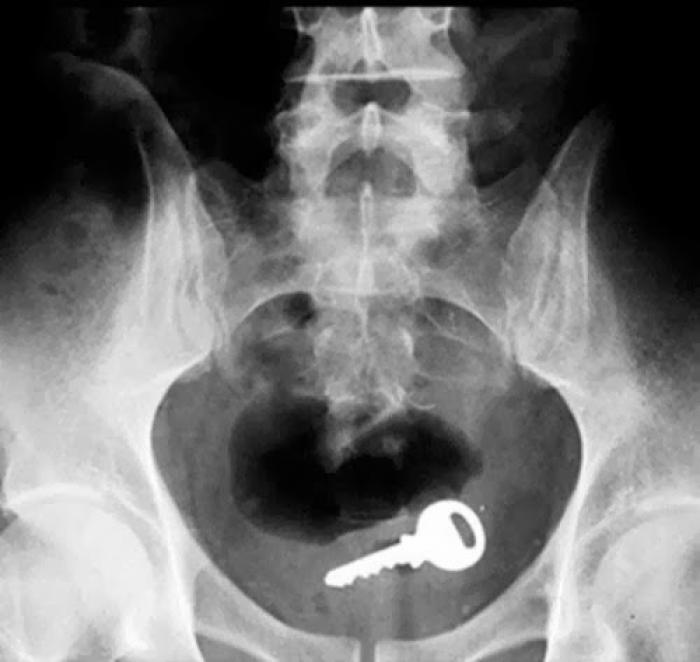

Razele X ne dovedesc că oamenii "pierd" adesea o mulțime de lucruri în propriul corp.